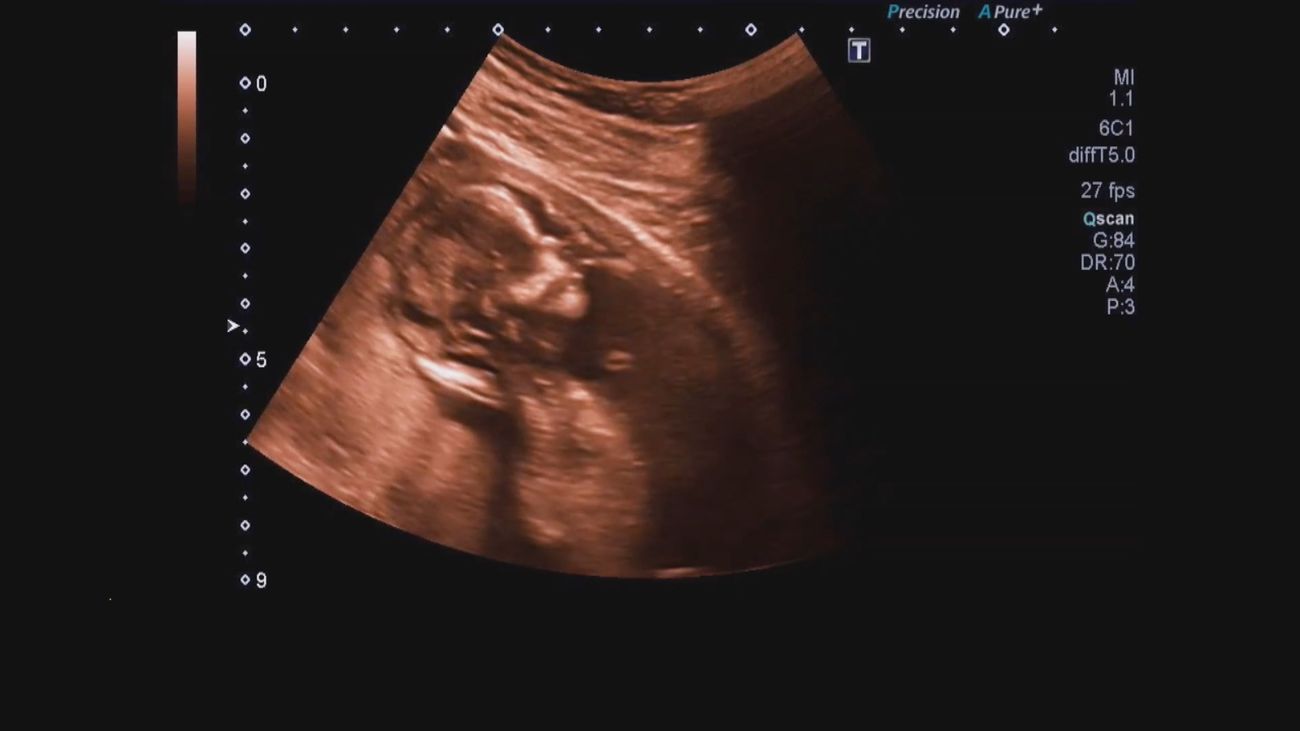

En Estados Unidos, una joven de 19 años embarazada ha sido asesinada para robarle a su bebé. La presunta asesina hizo pasar al recién nacido por su hijo.

Los hechos sucedieron en Chicago, donde la chica fue vista por última vez. Acudió a una casa donde, supuestamente le iban a regalar ropa para su bebé, pero allí fue ahorcada con un cable.

Al parecer, la distrajeron con un álbum de fotos, y le sacaron al bebé. Después llamaron a una ambulancia asegurando que había dado a luz. El niño se encuentra en coma.